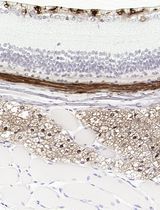

We have established a method using both centriolar protein CEP135 and PCM protein γ-Tubulin together as centrosome markers. We multiplexed centrosome markers with cell-cell junction markers to quantify centrosomes on a single cell level by high resolution microscopy (Wang et al., 2019a). We have tested different centriolar and cell-cell junction markers. Cell-cell junction proteins like E-Cadherin and α6 integrin are used to distinguish single cells from the neighbor cells and to identify the whole cell volume (Figure 1A). Foci with both centriolar proteins and PCM proteins are considered as centrosomes. Using this method, we have successfully performed centrosome quantification on a variety of normal and cancer tissues (Wang et al., 2019a; Wang et al., 2019b). Further, this method can be used to detect cells with centrosome amplification in both interphase and mitotic cells (Figure 1B). Here, we describe a detailed protocol to perform this method.

Figure 1. Centrosomes in human normal and cancer tissue. A. A human normal tonsil FFPE tissue sample stained with CEP135 (red) and E-Cadherin (green). Nuclei in blue. Scale bars: 10 μm. B. A human triple-negative breast cancer FFPE tissue sample stained with CEP135 (red), γ-Tubulin (green) and E-Cadherin (green). Nuclei in blue. Scale bars: 10 μm. Arrowheads indicate centrosomes.